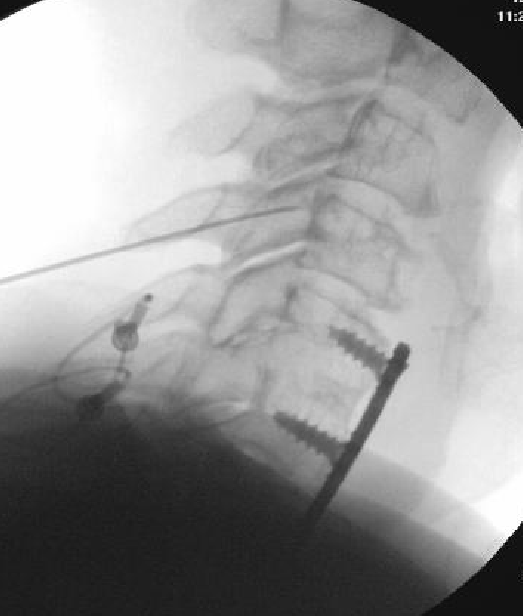

Nasty neuritis. This is 80 degrees 90 seconds.

These images look great. Sorry it happened? Steroid?

Lyrica Rx sent in, and we're starting it for chronic pain (and neuritis). She gets a shoulder scope in two weeks for a large RCT. I like antineuropathics (gabapentin 100mg HS or BID) perioperatively in general. I wish they were given 2 weeks before and after ALL orthopedic surgeries.

Dexamethasone given before RFA needles were removed.